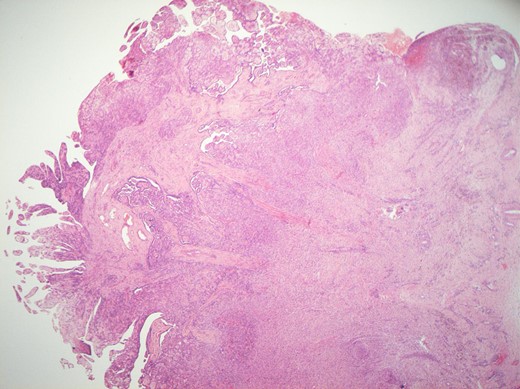

Histological features of the specimen were that of a fibrous cyst wall covered by cuboidal cells with bland nuclei (Fig. 1). Within the cystic space, there were branching, papillary structures with a fibrovascular core, lined with a single layer of bland cuboidal cells (Fig. 2). The stroma was oedematous and hyalinised. No sub-epithelial invasion was seen. There was no unequivocal cytologic atypia or atypical mitosis.

H&E staining of the specimen demonstrating a fibrous cyst wall covered by cuboidal cells with bland nuclei.